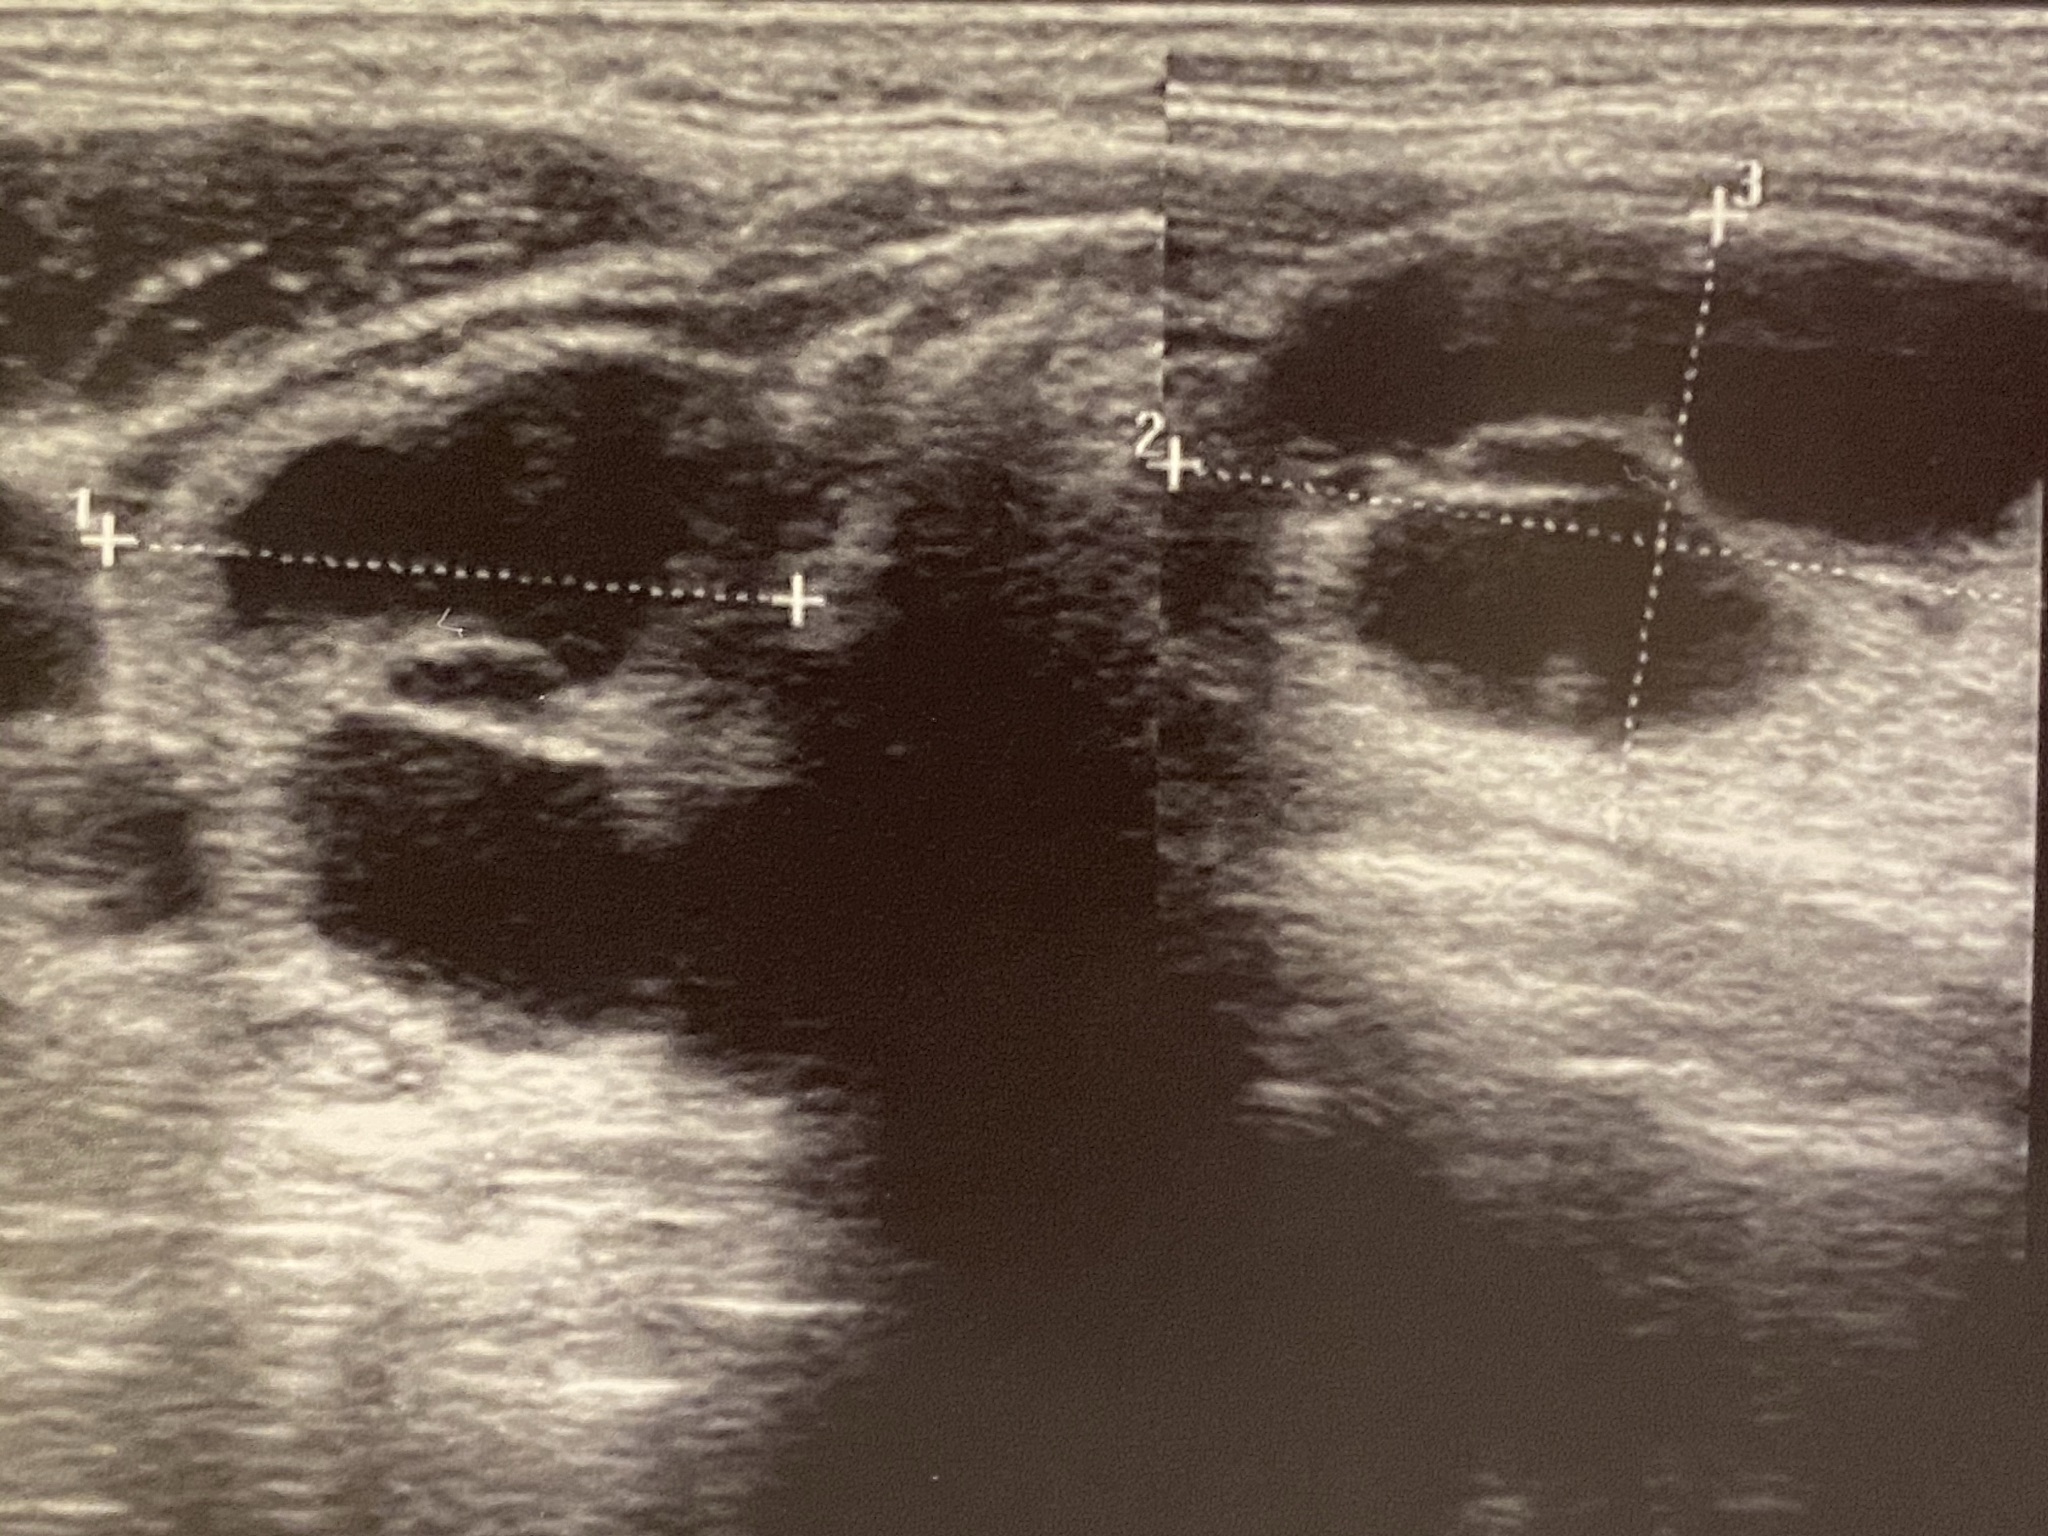

甲状腺球蛋白(Thyroglobulin)是一种在甲状腺中合成的大型蛋白质,其分子量约为660 kDa。它是甲状腺合成甲状腺素(thyroxine,T4)和三碘甲状腺原氨酸(triiodothyronine,T3)的前体蛋白。甲状腺球蛋白通过甲状腺细胞分泌到甲状腺的小泡中,然后在小泡中被碘化,产生T4和T3。甲状腺球蛋白也可以被检测出来,用于甲状腺癌的诊断和监测。